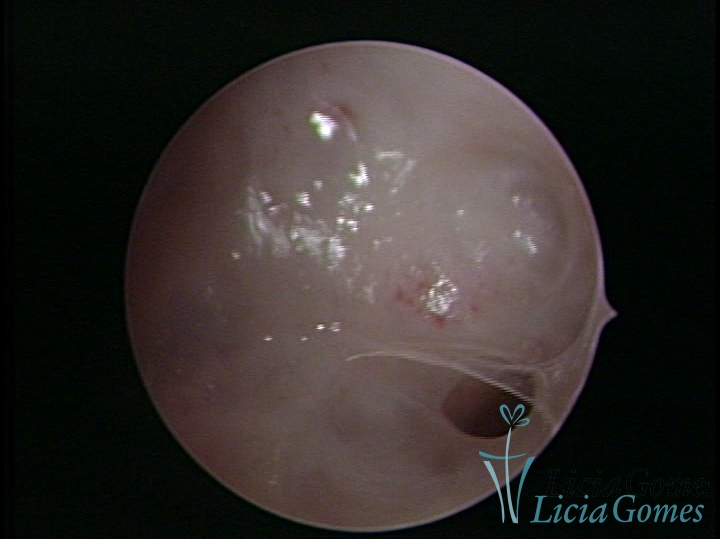

• SINÉQUIA TIPO FIBROMUSCULAR